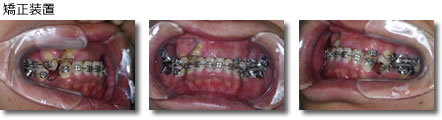

画像引用元:アイウエオ矯正歯科医院(https://www.aiueo-kyousei.com/c03/ortho_case_shingaku_top/ortho_case_shingaku_01)

メタルブラケットで歯の凹凸を矯正し、ゴムの力で下の歯を内側に矯正していきました。矯正期間は3~4週間に1回、保定期間は4~6ヶ月に1回程度の通院で治療。矯正には2年8ヶ月かかっています。